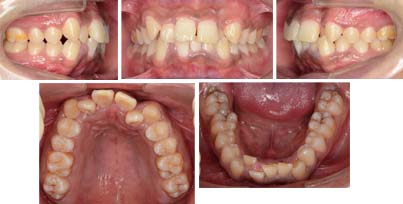

来院時の写真

歯が全体に大きいです。前歯が正中離開していて、全体に叢生が見られます。下の前歯は重なっています。リンガルブラケットで見えない矯正治療をご希望で来院されました。